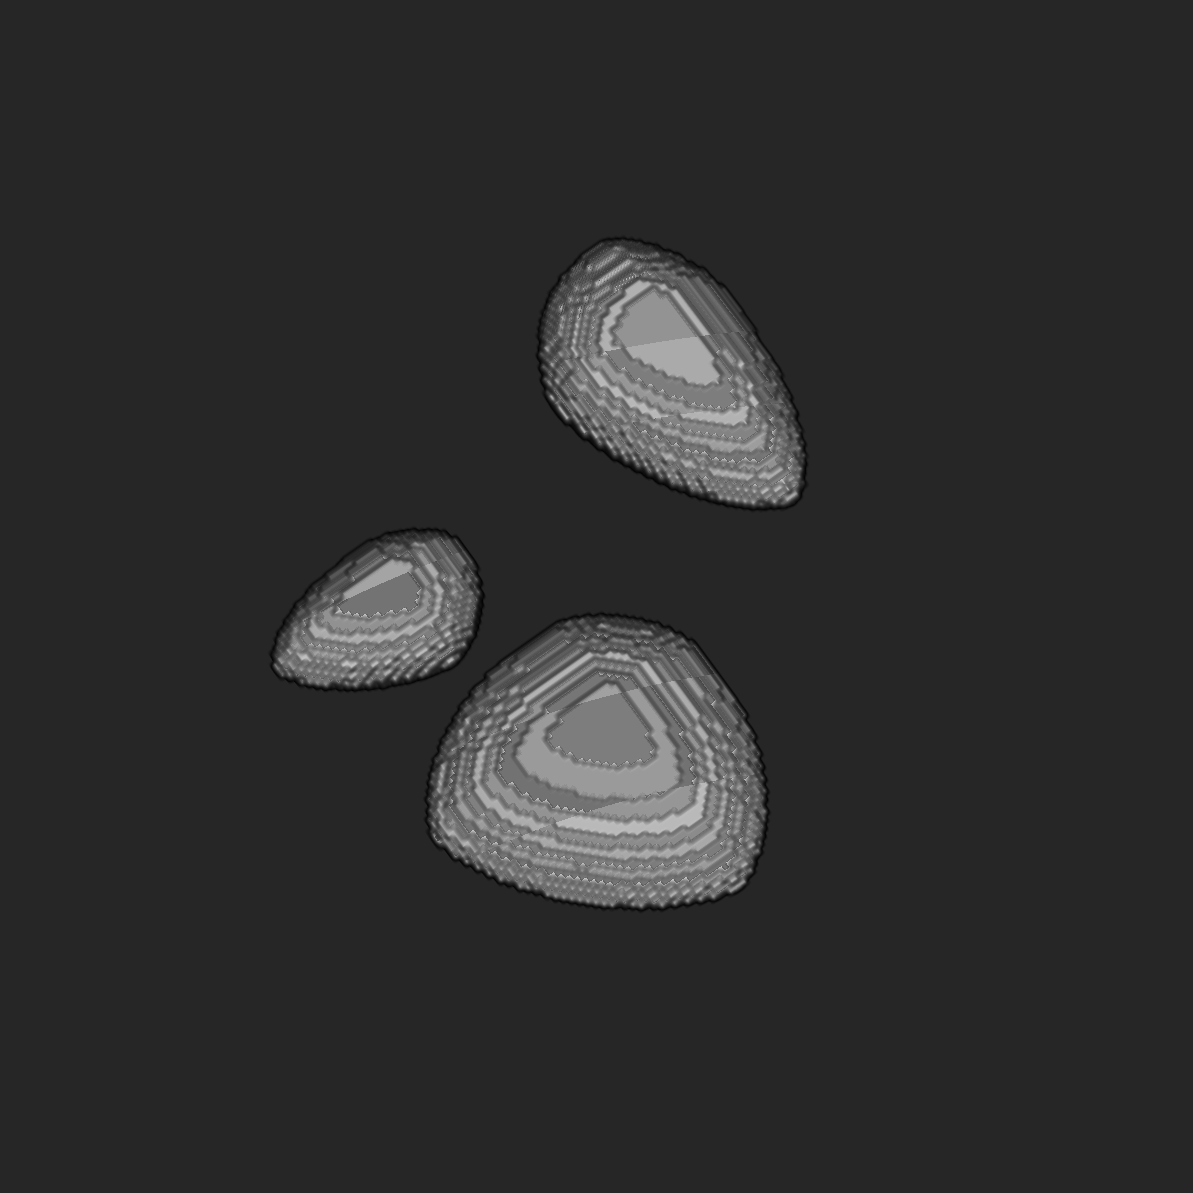

For testing our proposed method, we created a three-dimensional phantom consisting of three -balls, where , in a constant background (see Figure 16). First, we simulated X-ray measurements of the phantom using a parallel-beam imaging geometry of a 40-degree opening angle with 50 projection images. We computed the PDFP reconstructions slice-by slice, separately for each -plane, treating each slice as an independent 2D tomographic reconstruction problem. The complex wavelet coefficients used for regularization were computed using Kingsbury Q-shift filters. Following the workflow explained in Figure 11, we learn the boundary estimate for each -slice. The learned boundary estimate is then overlayed on the PDFP reconstruction to indicate the extent of boundaries of the stretched features in the reconstruction.

In Figure 17, a reconstructed -slice with the learned boundary estimate is compared to the ground truth -slice of the test phantom. Also, the tomosynthesis reconstruction is shown for comparison. The results of additional -slices are shown in Figure 18. To measure how well the learned boundary estimate matches the true boundary, we have computed the dice similarity coefficient (DSC) of segmentations computed from the learned boundary estimate () and compared those to the ground truth slice ():

where are the cardinalities, that is, the number of elements in the sets. The resulting DSC values are presented in table 1.

5.2 Reconstructions in the -plane

For a three-dimensional phantom, after independently computing PDFP reconstructions and the boundary estimates for each of the -slices separately (see section 5.1), we can stack the reconstruction results back together to form a volume. Then, we can slice the reconstructed volume in the -direction. We present the results as -slices with a selection of different -values. Reconstruction results of several -slices of the phantom are shown in Figure 19.

We trained our method with simulated elliptical targets in D. Our data was severely limited with a 40-degree angle-of-view. We found that the method generalizes successfully to 2D problems arising from slices of simulated -ball targets in . Namely, the extent of objects in the direction of the -axis was rather accurately recovered. However, the method did have difficulties near places where the boundaries of -balls had high curvature. We also noted that if some inclusions were much smaller than others (or of less contrast), the method might not detect them.